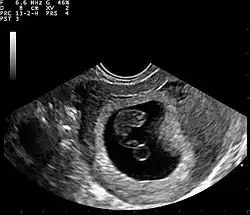

Ultrasound

Obstetric ultrasonography may also be used to detect and diagnose pregnancy. It is very common to have a positive at-home urine pregnancy test before an ultrasound. Both abdominal and vaginal ultrasound may be used, but vaginal ultrasound allows for earlier visualization of the pregnancy. With obstetric ultrasonography the gestational sac (intrauterine fluid collection) can be visualized at 4.5 to 5 weeks gestation, the yolk sac at 5 to 6 weeks gestation, and fetal pole at 5.5 to 6 weeks gestation. Ultrasound is used to diagnose multiple gestation, which cannot be diagnosed based on the presence of hCG in urine or blood.[15] Determination of the gestational age of the embryo/fetus is an additional benefit of ultrasound compared to hCG tests.[16]

Ultrasound is also a common tool for determining viability and location of a pregnancy. Serial ultrasound may be used to identify non-viable pregnancies, as pregnancies that do not grow in size or develop expected structural findings on repeated ultrasounds over a 1–2 week interval may be identified as abnormal.[29] Occasionally, a single ultrasound may be used to identify a pregnancy as non-viable; for example, an embryo that is greater than a certain size but that lacks a visible heart beat may be confidently determined to be not viable without the need for follow up ultrasound for confirmation.[29]